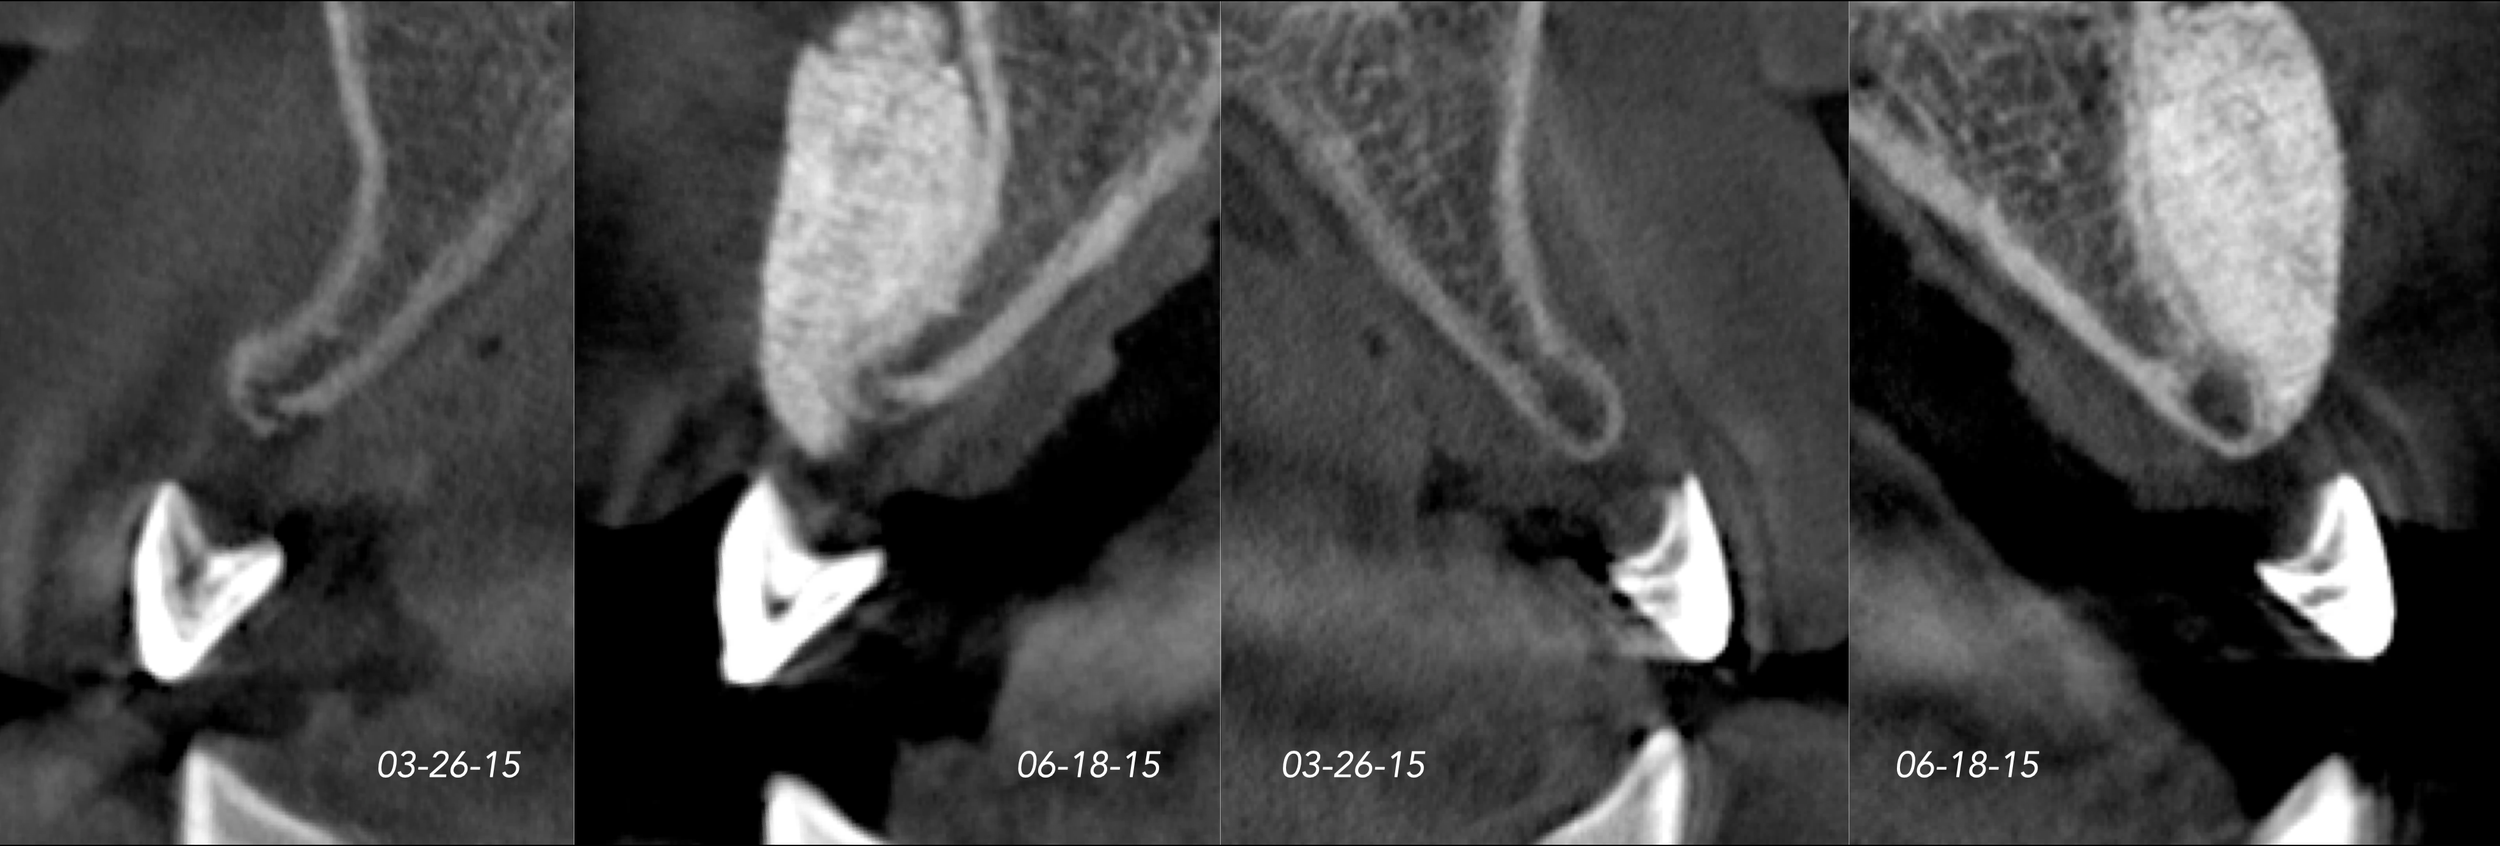

CASE 2. CONGENITALLY MISSING LATERAL INCISORS